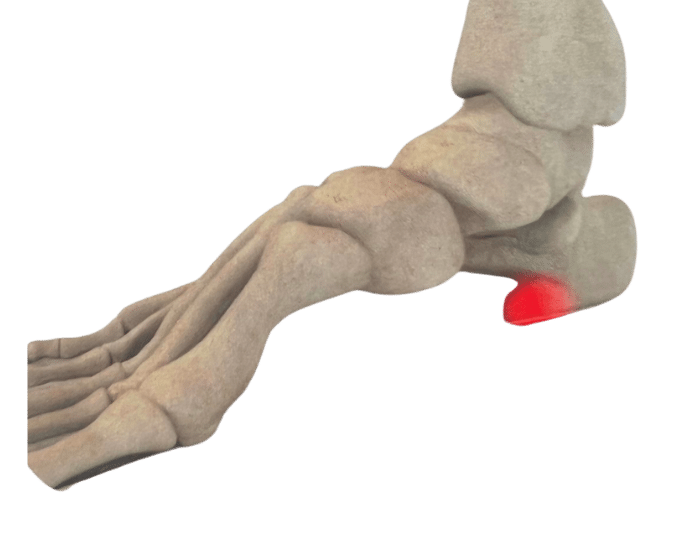

There are numerous reasons why you might need Custom Foot Orthotics. If you have pain in your foot, heel, knee or hip, have high arches or flat feet; or just being regularly on your feet and are getting any aches or pains in the feet or legs, or suffering from general foot pain while walking, running, playing sports or even at rest you qualify for Custom Foot Orthotics.